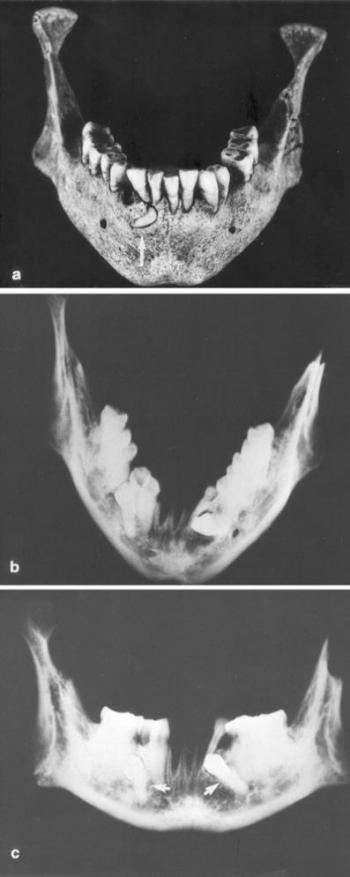

- 9. A fogazat betegségei